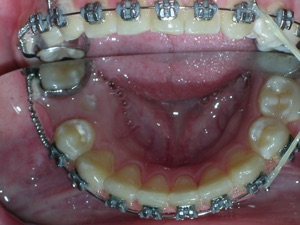

Here are the results.

Hope you like it too!